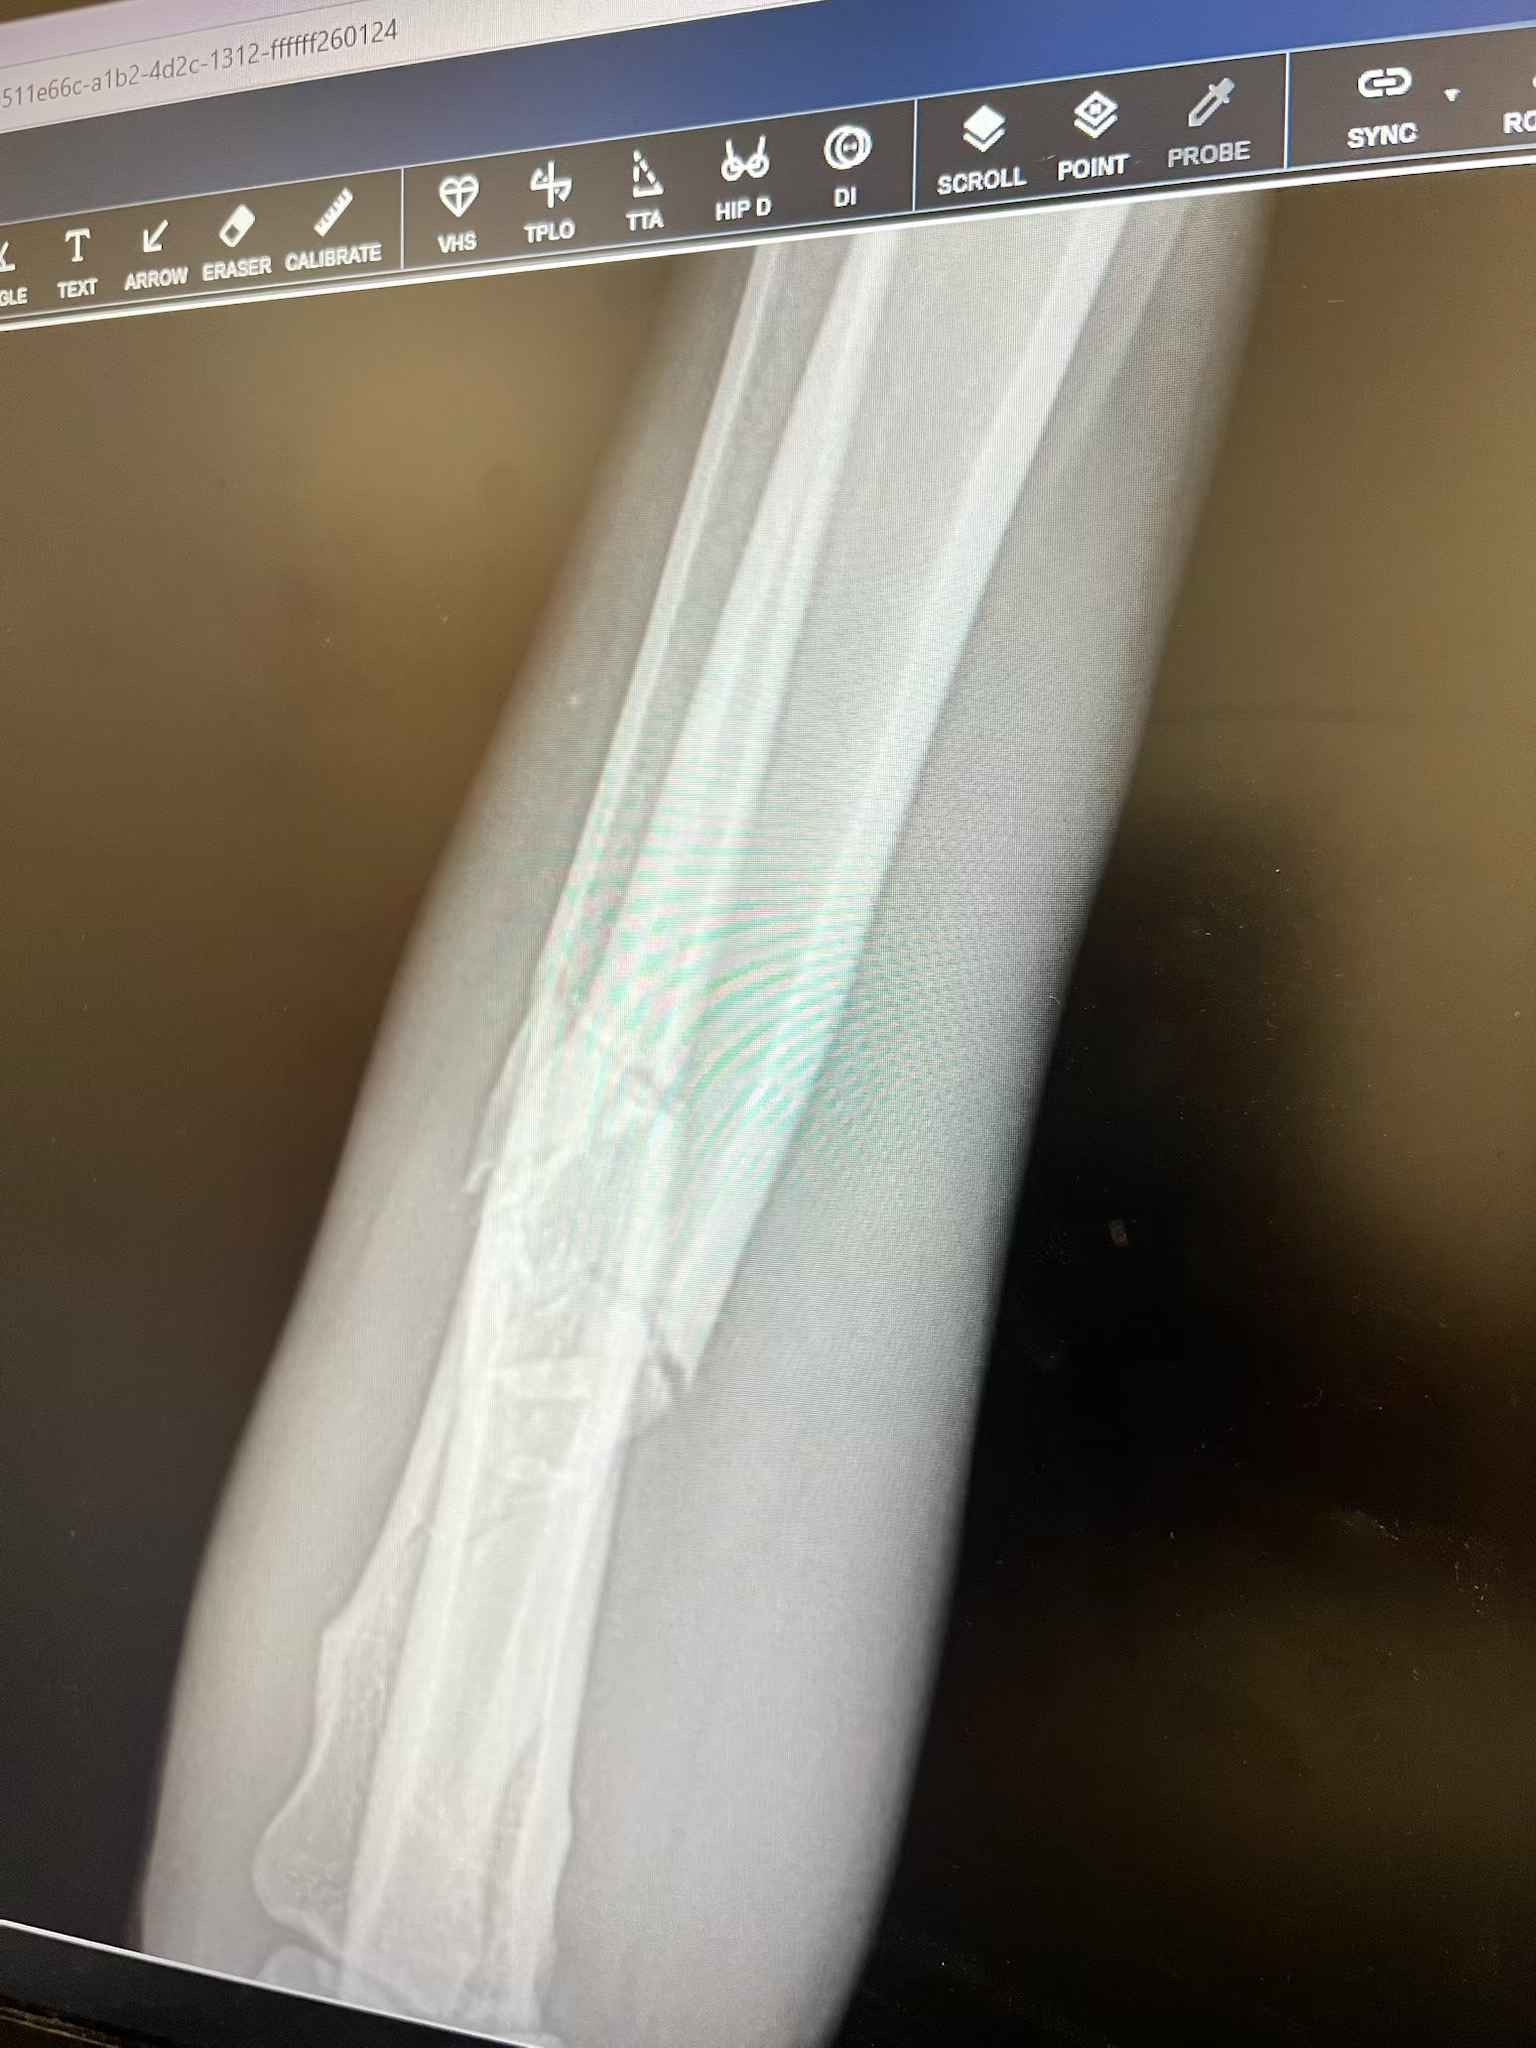

Our beloved boy, Trooper, was seriously injured in an accident and suffered a severe leg fracture. He’s in pain and needs urgent veterinary care and surgery to heal properly and avoid permanent damage.